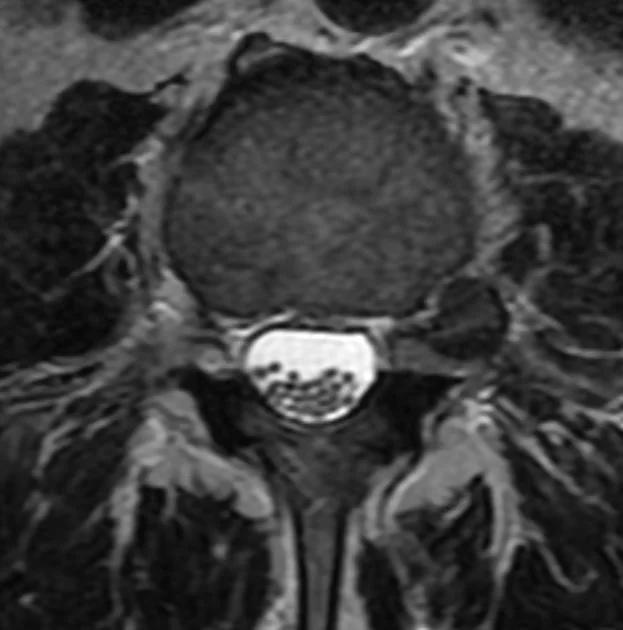

Πολλαπλά σβαννώματα (Νευρινώματα) οσφυϊκής μοίρας σπονδυλικής στήλης

Ασθενής άνδρας 75ετών με έντονο πόνο χαμηλά στη μέση, ιδίως κατά το κάθισμα. Επιπλέον, πόνος και στα δύο πόδια, ιδίως αριστερά, με έντονο μούδιασμα, το